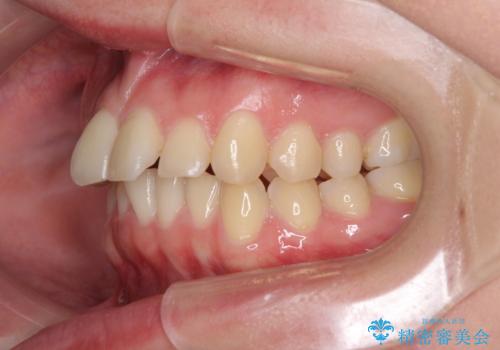

- 食いしばりが気になっていたとのことで来院された患者様です。

当初は睡眠時のマウスピースのみの製作をご希望でしたが、矯正治療の提案をしたところ、インビザラインにて矯正治療を行うこととなりました。

矯正治療中に食いしばりがより強くなることがあるため、半年に1回のペースでボツリヌストキシンによる咬合力緩和を並行して行うこととしました。

咬合力の緩和と食いしばりがちな咬み合わせが改善され、顎の負担が大幅に軽減されました。